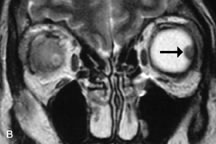

On MRI, uveal melanomas have a typical appearance that helps to differentiate them from other primary and secondary intraocular tumors as well as choroidal detachments. Pigmented melanomas are hyperintense on Tl-weighted images, hypointense on T2-weighted studies, and hyperintense on proton density–weighted examinations (Fig. 24).30,31,50,80–82 These signal characteristics have been attributed to the paramagnetic properties of melanin because of stable free radicals that shorten the T1 and T2 relaxation times. Moderate enhancement is seen on postgadolinium T2-weighted images. Gadolinium-enhanced T1-weighted images are particularly sensitive in detecting choroidal melanomas.83 MRI may be less sensitive in detecting extrascleral extension of tumor than echography performed by an experienced ultrasonographer.84

Fig. 24. A. T1- and (B) T2-weighted MR scans demonstrate a small nodular intraocular mass (arrows) that is very hyperintense on the T1-weighted scan and hypointense on the T2-weighted image. This signal intensity pattern is due to the presence of free radicals within melanin granules. C and D. Postcontrast fat-suppressed T1-weighted scans demonstrate homogeneous intense enhancement of the lesion and no evidence of seleral penetration or optic nerve invasion.